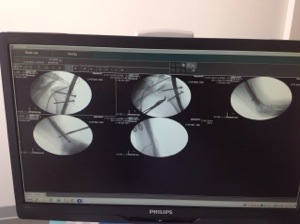

Vanmorgen hebben we de foto’s bekeken van mijn arm met de pen er in.

Op de foto is te zien hoe de pen met 2 schroeven aan de bovenkant en onder met 1 schroef is vastgezet. Raar idee dat ze zo bezig zijn geweest.